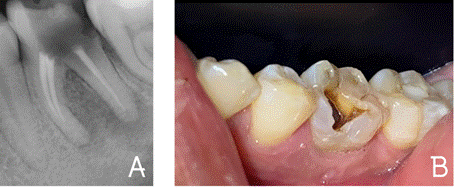

exploración clínica (Figura 1 A) y radiográfica (Figura 1 B), se observó el

órgano dental 36 con tratamiento de conductos presente y lesión extensa que

comunica con furca; el pronóstico es pobre, por lo que se toma la decisión

llevar a cabo la extracción de la pieza dental.

Figura 1.

A) Fotografía clínica preoperatoria. B) Radiografía periapical

inicial.